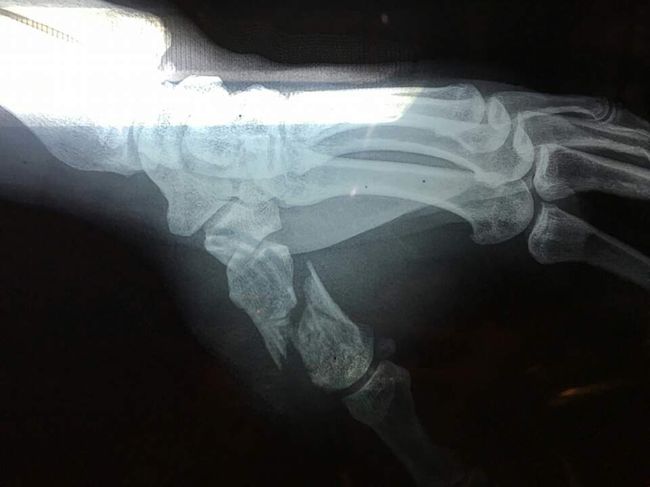

16일 중국 베이징공인체육관에서 열린 샤오미 로드FC 030 무제한급 4강전서 명현만에 KO 승을 거둔 마이티 모(미국)의 왼쪽 엄지 손가락이 골절됐다.

17일 로드FC는 "마이티 모가 경기를 마친 뒤 병원 검진 결과 왼쪽 엄지손가락 골절을 당한 것으로 나타났다"면서 "로드FC 링 닥터인 정병원 정우문 원장에 따르면 최소 4개월에서 7개월 정도 회복 기간이 필요한 것으로 나타났다"고 밝혔다.

마이티 모는 "1라운드 펀치 공방 중 부러진 것 같다. 아팠지만 골절까지 이어진 줄은 몰랐다. 그래서 그라운드 전력을 썼고 승리했다"고 밝혔다.

또 그는 "오히려 골절이 깔끔하게 되어 회복하는데 큰 어려움은 없을 것"이라고 전했다.

부상을 당한 마이티 모는 일단 압박붕대로 고정 후 미국으로 돌아가 수술을 받을 예정이다.

[사진] 로드FC 제공.